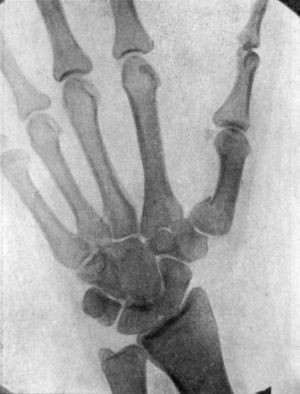

109 49.Radiogram showing Fracture of Navicular (Scaphoid) Bone

111 50.Dorsal Dislocation of Wrist at Radio-carpal Articulation